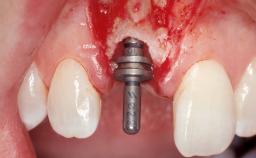

Immediate Flapless Placement of an Implant in a Maxillary Left Central Incisor Site

Placement Protocol Immediate implant placement

Tooth Site Maxillary incisor or canine

Socket Morphology Single-root socket

Socket Integrity Damage to one or more bone walls